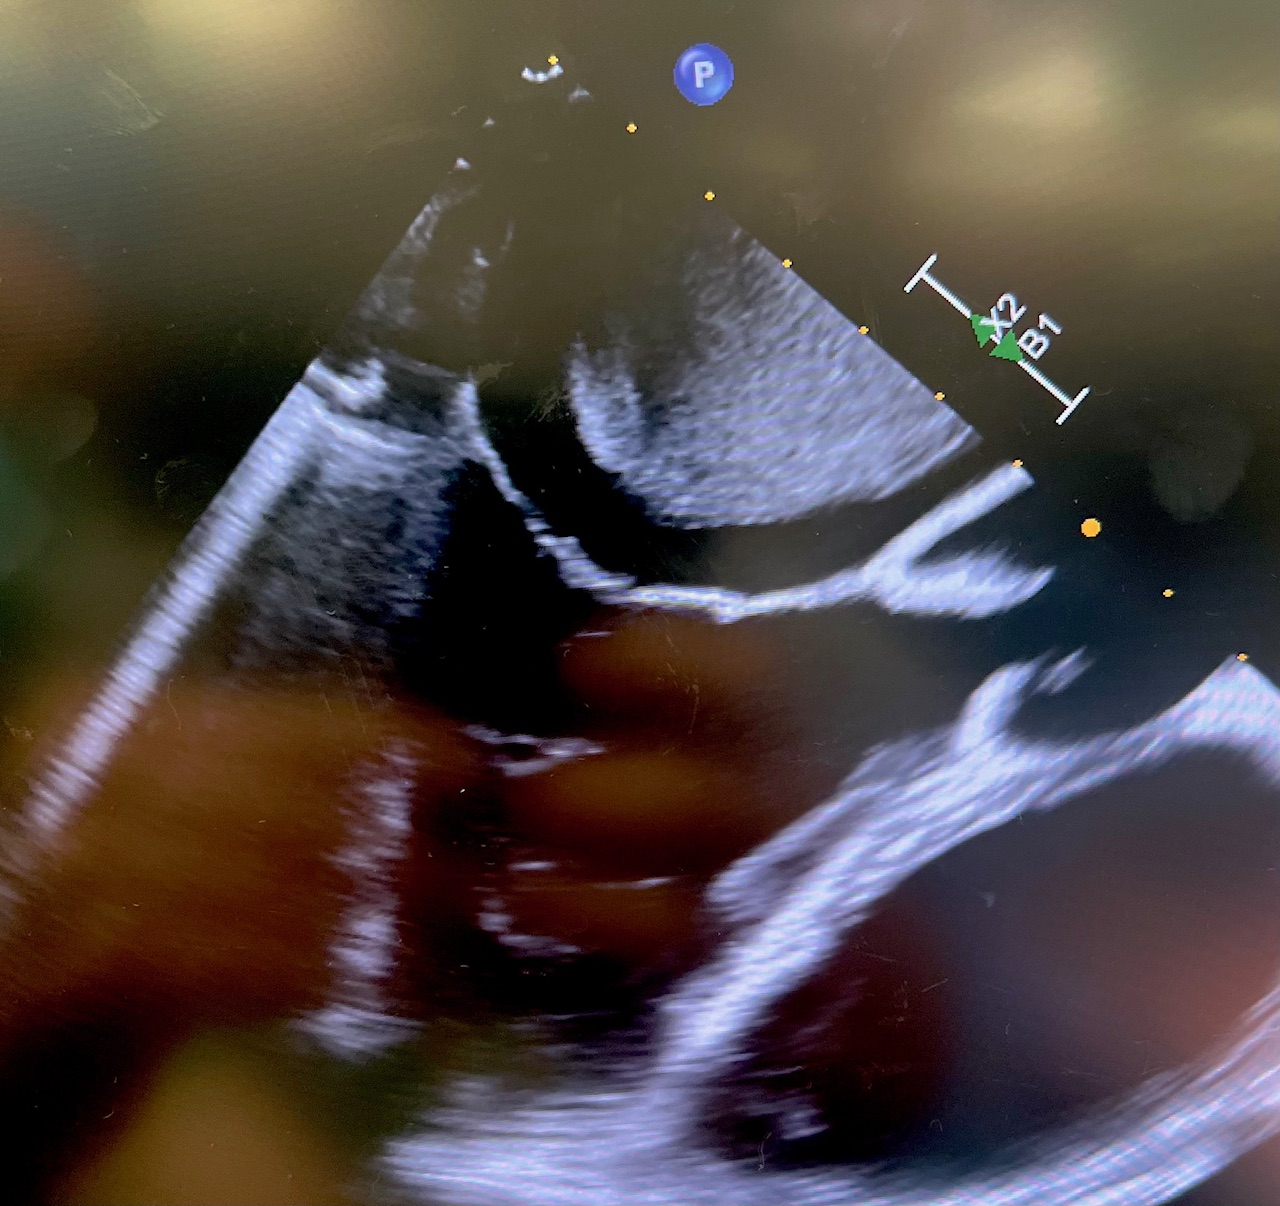

TTE revealed a large echogenic left atrial mass (measuring about 4.5 cm x 8.2 cm) that appeared attached to interatrial septum. The initial impression was atrial myxoma. Differential diagnosis included thrombus or other cardiac tumor. The mass was protruding into mitral valve orifice during diastole, causing functional mitral stenosis. The anterior mitral leaflet was thickened, in particular, at the leaflet tip, indicating a possible rheumatic mitral valve. The patient also had moderate mitral valve regurgitation.

The mass was resected en bloc with the septum. The mitral valve was repaired with a 32 mm CG Future band (Medtronic). The interatrial septum was reconstructed with autologous pericardium. The tricuspid valve was repaired with a Kay annuloplasty. Postoperatively, the patient remained with severe right ventricular dysfunction requiring open chest and central venoarterial extracorporeal membrane oxygenation (VA ECMO) which was successfully weaned on postoperative day 5. Intra-operative echo provided exceptional images of the myxoma, in addition to displaying the nearly complete obstruction of the left atrial outflow tract (Figure 3, Video 2).

Video 2. Intra-operative echo with myxoma.